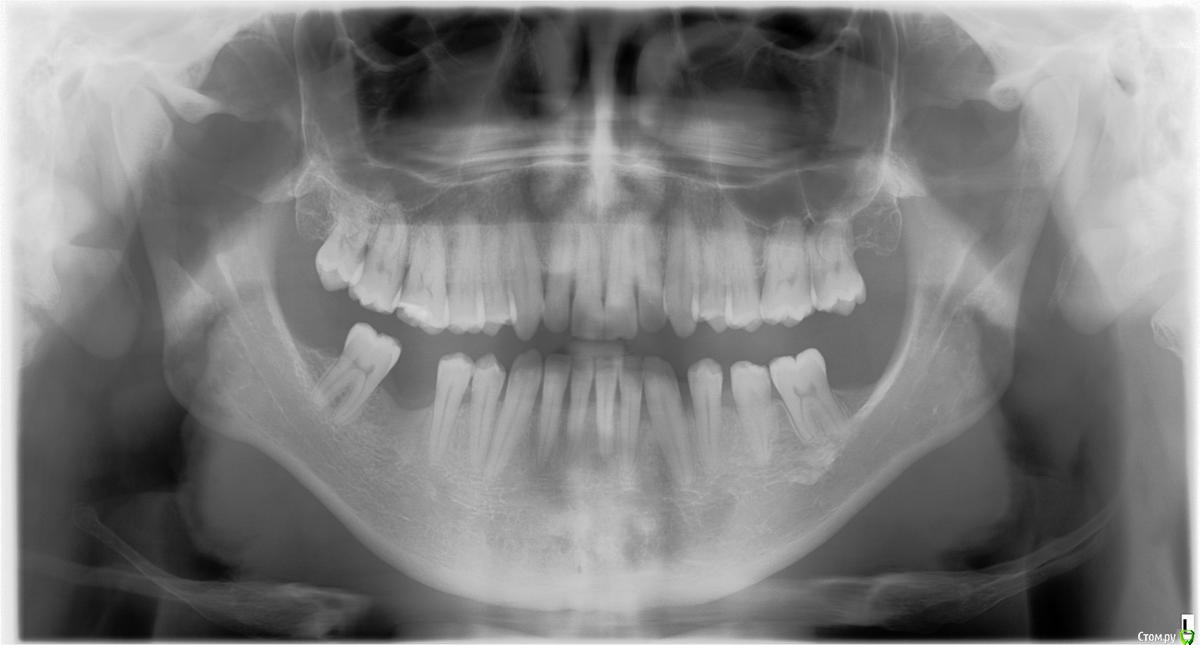

Kukloma Опубликовано 1 апреля, 2016 Поделиться Опубликовано 1 апреля, 2016 Здравствуйте, Буду рад за любой совет и (здесь или в личку) контакты ортодонта, который специализируется по таким проблемам. Вкратце, проблема в несмыкании верхних и нижних зубов с левой стороны при закрытии рта. Кроме того, 10 лет назад было не очень удачное ортодонтическое лечение, в итоге есть риск, что если зубы опять двигать куда-то, то они могут расшататься. Не знаю, видна на них проблема или нет - на всякий случай прикрепляю два недавних снимка Ходил уже к нескольким ортодонтам, и что-то определенного они мне не посоветовали. Кто-то говорит иди к ортопеду, чтобы коронками наращивать недостающее расстояние между низом и верхом. Кто-то говорит идти к хирургу. Сходил к ортопеду, сказал иди к ортодонту. Получается замкнутый круг. Похоже, попадаю на тех, кто берется за стандартные проблемы, а не готовы рисковать занимаясь нетривиальной проблемой. Буду признателен за любой совет - и к специалисту какого направления обратиться (ортодонт, хирург) и, особенно, конкретные имена сильных специалистов. Спасибо заранее! Ссылка на комментарий